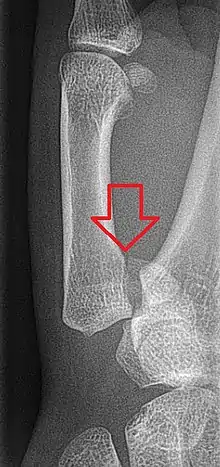

Bennett's fracture

The Bennett fracture is an oblique intraarticular metacarpal fracture dislocation, caused by an axial force directed against the partially flexed metacarpal. This type of compression along the metacarpal bone is often sustained when a person punches a hard object, such as the skull or tibia of an opponent, or a wall. It can also occur as a result of a fall onto the thumb. This is a common injury sustained from bike falls, as the thumb is generally extended while around the handle bars. It is also a common injury in car crashes, especially into fixed objects, from the driver holding the steering wheel during impact. The hand moves forward, while the steering wheel rim hyperextends the thumb. Some authors have recently made an assertion against popular belief that the APL tendon is not a deforming force on the Bennett fracture.[3]